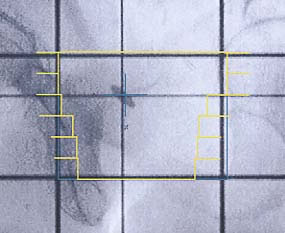

Prostatakarzinom: Simulationsaufnahme

Einführung aktuelle Bilder - Einführung Bestrahlungspläne - Einführung Demonstration